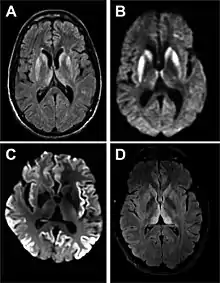

Magnetic resonance image of sporadic CJD[2]

Through the image of MRI, the obvious precipitation of prion protein in the brain is visible.

• MRI of the brain – often shows high signal intensity in the caudate nucleus and putamen bilaterally on T2-weighted images.

Imaging of the brain may be performed during medical evaluation, both to rule out other causes and to obtain supportive evidence for diagnosis. Imaging findings are variable in their appearance, and also variable in sensitivity and specificity.[43] While imaging plays a lesser role in diagnosis of CJD,[44] characteristic findings on brain MRI in some cases may precede onset of clinical manifestations.[45]

Brain MRI is the most useful imaging modality for changes related to CJD. Of the MRI sequences, diffuse-weighted imaging sequences are most sensitive.[46] Characteristic findings are as follows:

dwMRI, FDG PET and post mortem histology from a patient who presented with sCJD aged 66

• Focal or diffuse diffusion-restriction involving the cerebral cortex and/or basal ganglia. In about 24% of cases DWI shows only cortical hyperintensity; in 68%, cortical and subcortical abnormalities; and in 5%, only subcortical anomalies.[47] The most iconic and striking cortical abnormality has been called "cortical ribboning" or "cortical ribbon sign" due to hyperintensities resembling ribbons appearing in the cortex on MRI.[48] The involvement of the thalamus can be found in sCJD, is even stronger and constant in vCJD.[49]

• Varying degree of symmetric T2 hyperintense signal changes in the basal ganglia (i.e., caudate and putamen), and to a lesser extent globus pallidus and occipital cortex.[44]

• Cerebellar atrophy

Brain FDG PET-CT tends to be markedly abnormal, and is increasingly used in the investigation of dementias.

• Patients with CJD will normally have hypometabolism on FDG PET.[50]